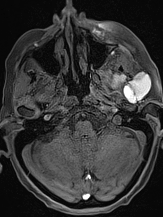

生命感知自由心脏成像平台

MAGNETOM Vida磁共振系统可实现全新的生命感知自由心脏成像:病人进行心脏扫描时,无需配套任何呼吸门控装置,在扫描过程中,磁共振会全程监测病人呼吸以及心电信号,实时控制信号采集;在BioMatrix生命矩阵系统的协助下,Vida可实现业界最快的心脏电影成像,比常规心脏电影成像快10-20倍,可以自由呼吸状态,一个心动周期完成电影采集。

磁共振矩阵怎么计算【重磅】新一代智慧型生命感知磁共振——MAGNETOM Vida, 成功落户中大放射并全面投入使用!!!_https://www.jmylbn.com_新闻资讯_第12张

磁共振矩阵怎么计算【重磅】新一代智慧型生命感知磁共振——MAGNETOM Vida, 成功落户中大放射并全面投入使用!!!_https://www.jmylbn.com_新闻资讯_第13张

生命感知的自由心脏电影

自由呼吸完成扫描,一个心动周期完成电影采集